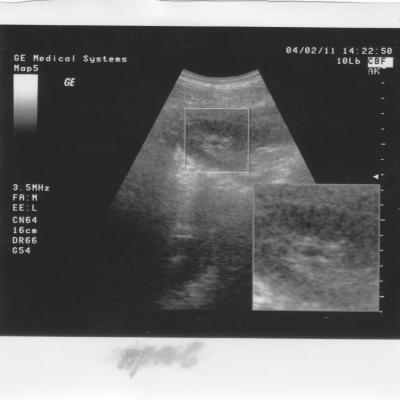

это камни или соли на снимке УЗИ

А в 2010 году на снимке видно что то в правой, не оперированой почке.Анализы все в норме.

В 2011 году сделаны снимки обеих почек на консультацию к урологу.Анализы все в норме.

Отправляю снимки УЗИ.